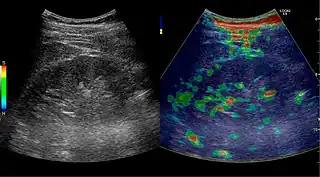

Solid malignant tumors in the kidney do not exhibit specific enhancement patterns like some liver lesions, and no valid enhancement criteria between benign and malignant renal lesions have been proposed. However, CEUS is used in some patients after ablation of renal cell carcinoma to evaluate contrast uptake in the treated area (Figure 30).

Figure 31. Unspecific cortical lesion on CT is confirmed cystic and benign with contrast-enhanced ultrasound (CEUS) using image fusion.[1]